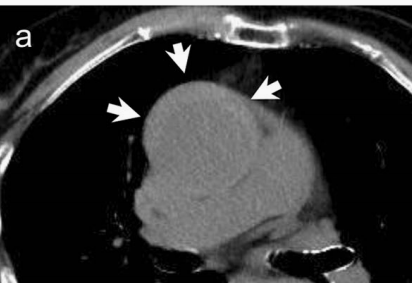

不行,你再看看,越看越像!

图13

增强CT一看,主动脉的确裂开了!

图14